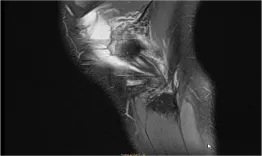

A 24-year-old female patient presents with hip pain. Pre-op X-rays reveal total lysis of the shelf: What causes the patient's symptoms and how would you manage this condition? The goals of this clinical case are to discuss the different indications and therapeutic options for a hip dysplasia in a young patient, as well as possible complications.

Hip dysplasia in a young woman: How should I treat?

Nicolas Reina